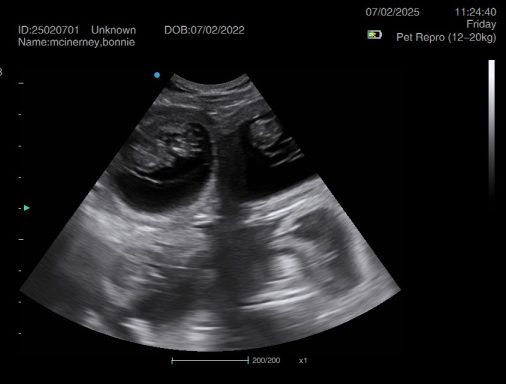

Ultrasound pregnancy scanning is a safe, non-invasive way to confirm pregnancy in dogs and cats, offering breeders and pet owners peace of mind and vital information to support responsible care. It allows us to detect gestational sacs, assess foetal development, and estimate litter size—all while ensuring the wellbeing of the animal.

Pregnancy can sometimes be detected as early as Day 18 post-mating, but scanning at this stage is not routinely recommended. Embryos are still developing and may not be clearly visible, and there is a natural risk of embryo resorption, which can lead to misleading or inconclusive results.

For the most accurate and reliable scan, we advise booking between Day 25 and Day 32, when pregnancy is more easily confirmed and foetal structures are clearer. If an early scan is performed and no pregnancy is detected, we offer a FREE complimentary re-scan after 7 days at the clinic to ensure clarity and support informed decision-making.

Our approach balances early insight with ethical care—always prioritizing the comfort of the animal and the accuracy of the results.

Gallery